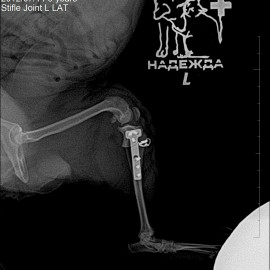

После проведенных исследований был поставлен диагноз: разрыв передней крестообразной связки левого коленного сустава, медиальный пателлярный вывих левого коленного сустава. Были проведены операции: артротомия левого коленного сустава, трохлеопластика блока левого бедра, дупкликатура капсулы коленного сустава, латеральная транспозиция шероховатости левой большеберцовой кости, латеральная траспозиция шероховатости большеберцовой кости, TPLO.

Снимок 2 после операции.